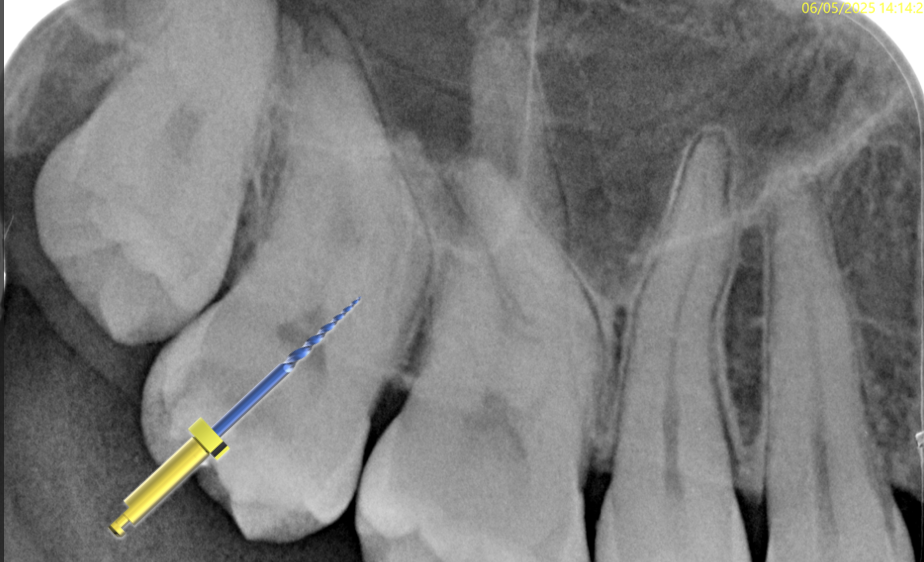

Fig. 5

I started with pre flaring the root canals by using the RR file (17/.10) in the coronal third